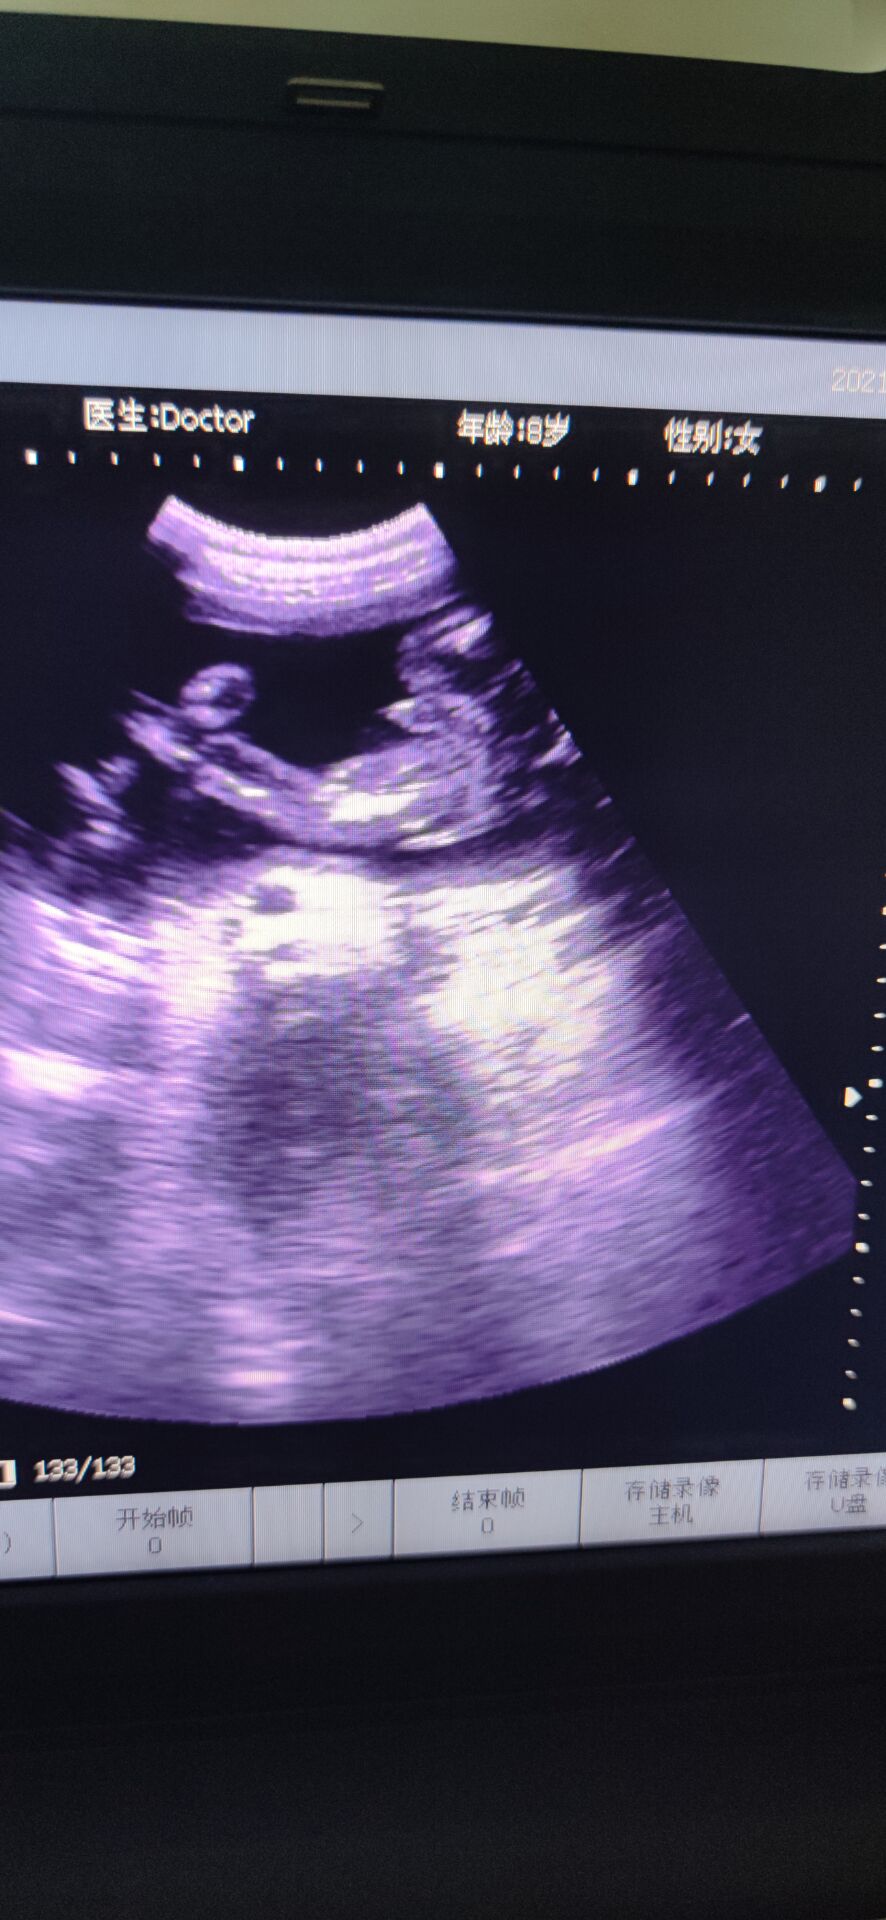

6月5日下午,分泌物有点血丝,而我在洗碗的时候,小腹有点点坠痛,但是休息下能缓解,到了晚上跟孕妇群的人聊了聊,不放心,挂急诊,B超做了好久,突然医生让我别动,就躺着,说:“你宫口已经开了,内宫口全开了,外宫口开了两指了,羊膜在阴道里,都快到阴道口了!”听到的那刻,突然就心慌紧张了,整个人都在发抖,腿也控制不住地抖,才26周啊,还没足月。产科的人立马下来把我拉到待产室内检,然后跟我说还没足月,什么都还没发育好,生下来就要立马进保温箱,要生下来起码得准备一百万…说了很多,大概意思都是劝我引产,可是我舍不得啊,我下不定决心,她们就破例让我老公进来,同样地话跟我老公说了一遍,但是我们想保,医生就给了建议,转入市人民医院,那里有紧急环扎术,当天晚上就转过去,中途医生给我上了抑制宫缩的药。转过去的时候已经是凌晨两点多了,医生说她们医院已经不做紧急环扎术了,她也不知道哪个医院能做,并且这么晚了,我再转院也是折腾,我这才26周,产科和妇科不会收的,只能收计划生育科,但是计划生育科是不会管我的,因为我这情况医学上说就是难免流产,打完从上一个医院带来的吊瓶后,是不会管我的,顺其自然。这不是我们想要的答案,医生说没有其他办法,我们也不知道该怎么办,想着先转计划生育科吧,当晚做的核酸,但是因为核酸报告没那么快出,所以把我放到了抢救室,期间打了一枚促肺针。那晚好煎熬啊,睡又睡不着,周围都是打吊瓶的人,临急出的门,手机又没什么电,又不敢乱动,躺的身子僵硬疼痛,又不能下床走动,老公给我买了包护理垫,上厕所就直接尿在护理垫上。好不容易熬到早上,核酸报告还没出,到了十点多也没出,我老公在网上查资料,打电话,看哪个医院可以做紧急环扎,他侧对着我坐着,我看到他哭了,默默在流泪,那时候真心疼他。好不容易市妇幼说她们医院可以做,但是不派车来接,人民医院也不派车送。怎么办呢,叫出租车吗?可是出租车会愿意拉我吗并且我还得躺着。我老公和我家公就出去联系私人救护车。出去了好久,我就躺在床上望着门口,一有人进来,我就以为是他们回来了,但是不是,是别的病人的家属,后来我借别人手机给他打电话,我说:“你不要离开太久,我一个人在这,我害怕[泣不成声]”我老公他们好不容易联系到私人救护车把我送到市妇幼,内检时医生说做不了紧急环扎了,我已经有宫缩了,只能打吊瓶,抑制宫缩。因为疫情原因,只能一个陪护,我老公做的核酸还没出报告,要明天才能出,所以临时请了个月嫂陪护我,那天已经是6月6日了,晚上睡觉的时候感觉尿尿那里湿湿的,一擦,有血丝,并且不是一点点,叫了医生,医生给我上了另一种抑制宫缩的药,没一会就心跳加速,医生说那药是会让心跳加速,还让我如果有宫缩要告诉她。那一整晚都睡不安稳,一整晚,时间才过去五分钟,感觉太难熬了。等到6月7日中午,我老公的核酸报告出来了,他终于可以进来陪护了,心里开心了一些,做了B超,显示是26+6周,980克。因为我们要保,所以儿科医生也过来跟我们说了些注意事项和风险,还安慰我说,我这孕周和宝宝体重也还好,她们治疗过很多早产儿,百分之九十都能健康平安出院,让我不要太担心。